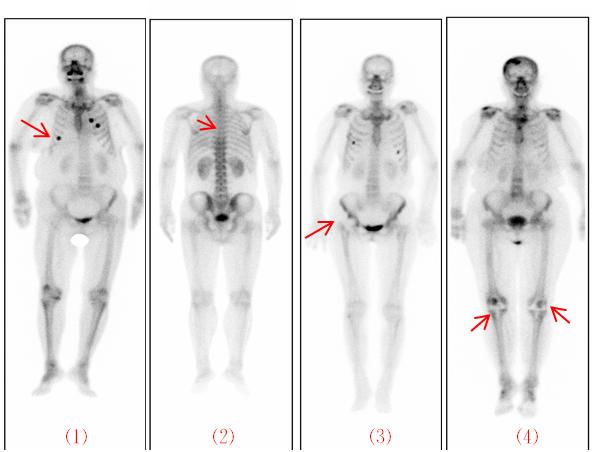

6、掃描時,保持全身不動

掃描時需躺平,保持全身不動約20分鐘。如掃描時有肢體移位,會出現重影、體位不對稱,有可能造成兩側放射性分布不對稱,影響圖像質量。